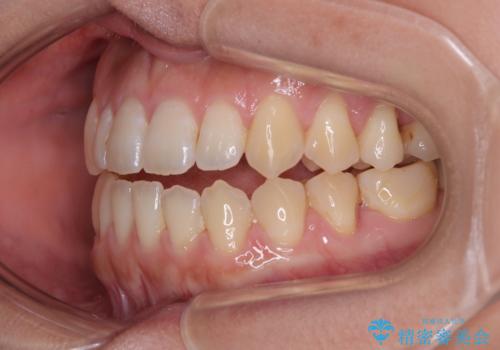

- 極端な開咬を気にして来院された患者様です。

開咬の方の特徴として、幼少期の指しゃぶりの癖や、強い舌の突出癖が挙げられます。

こちらの患者様も強い舌の突出癖が認められたため、矯正治療を行うにあたり、舌のトレーニングをしっかりと行っていただくように指示をいたしました。

開咬はインビザラインが得意とする歯列不正であるため、舌のトレーニングを行いながら、インビザラインにて矯正治療を行うこととしました。

担当医としては、もっと上下の前歯を接触させるところまで治療を進めたいという思いがありますが、今まで咀嚼できなかったものが食べられるようになったということで、この状態で治療終了となりました。